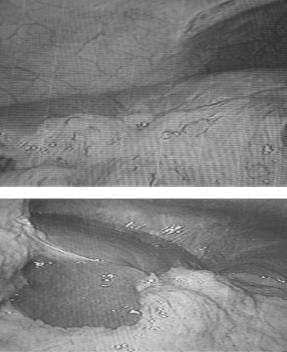

Después de resecar el techo de los quistes, debido a la cantidad del líquido drenado y teniendo en cuenta que no se fijó epiplón en su interior, se dejaron sendos drenes, para evaluar las características del líquido que pudiera drenar y evitar su acumulación en caso de ser bilioso. En el control laparoscópico se observó la migración del epiplón hasta el lecho de estos quistes y su incorporación a los mismos (figura 3).

FIGURA 3. Migración de epiplón al lecho de los quistes.